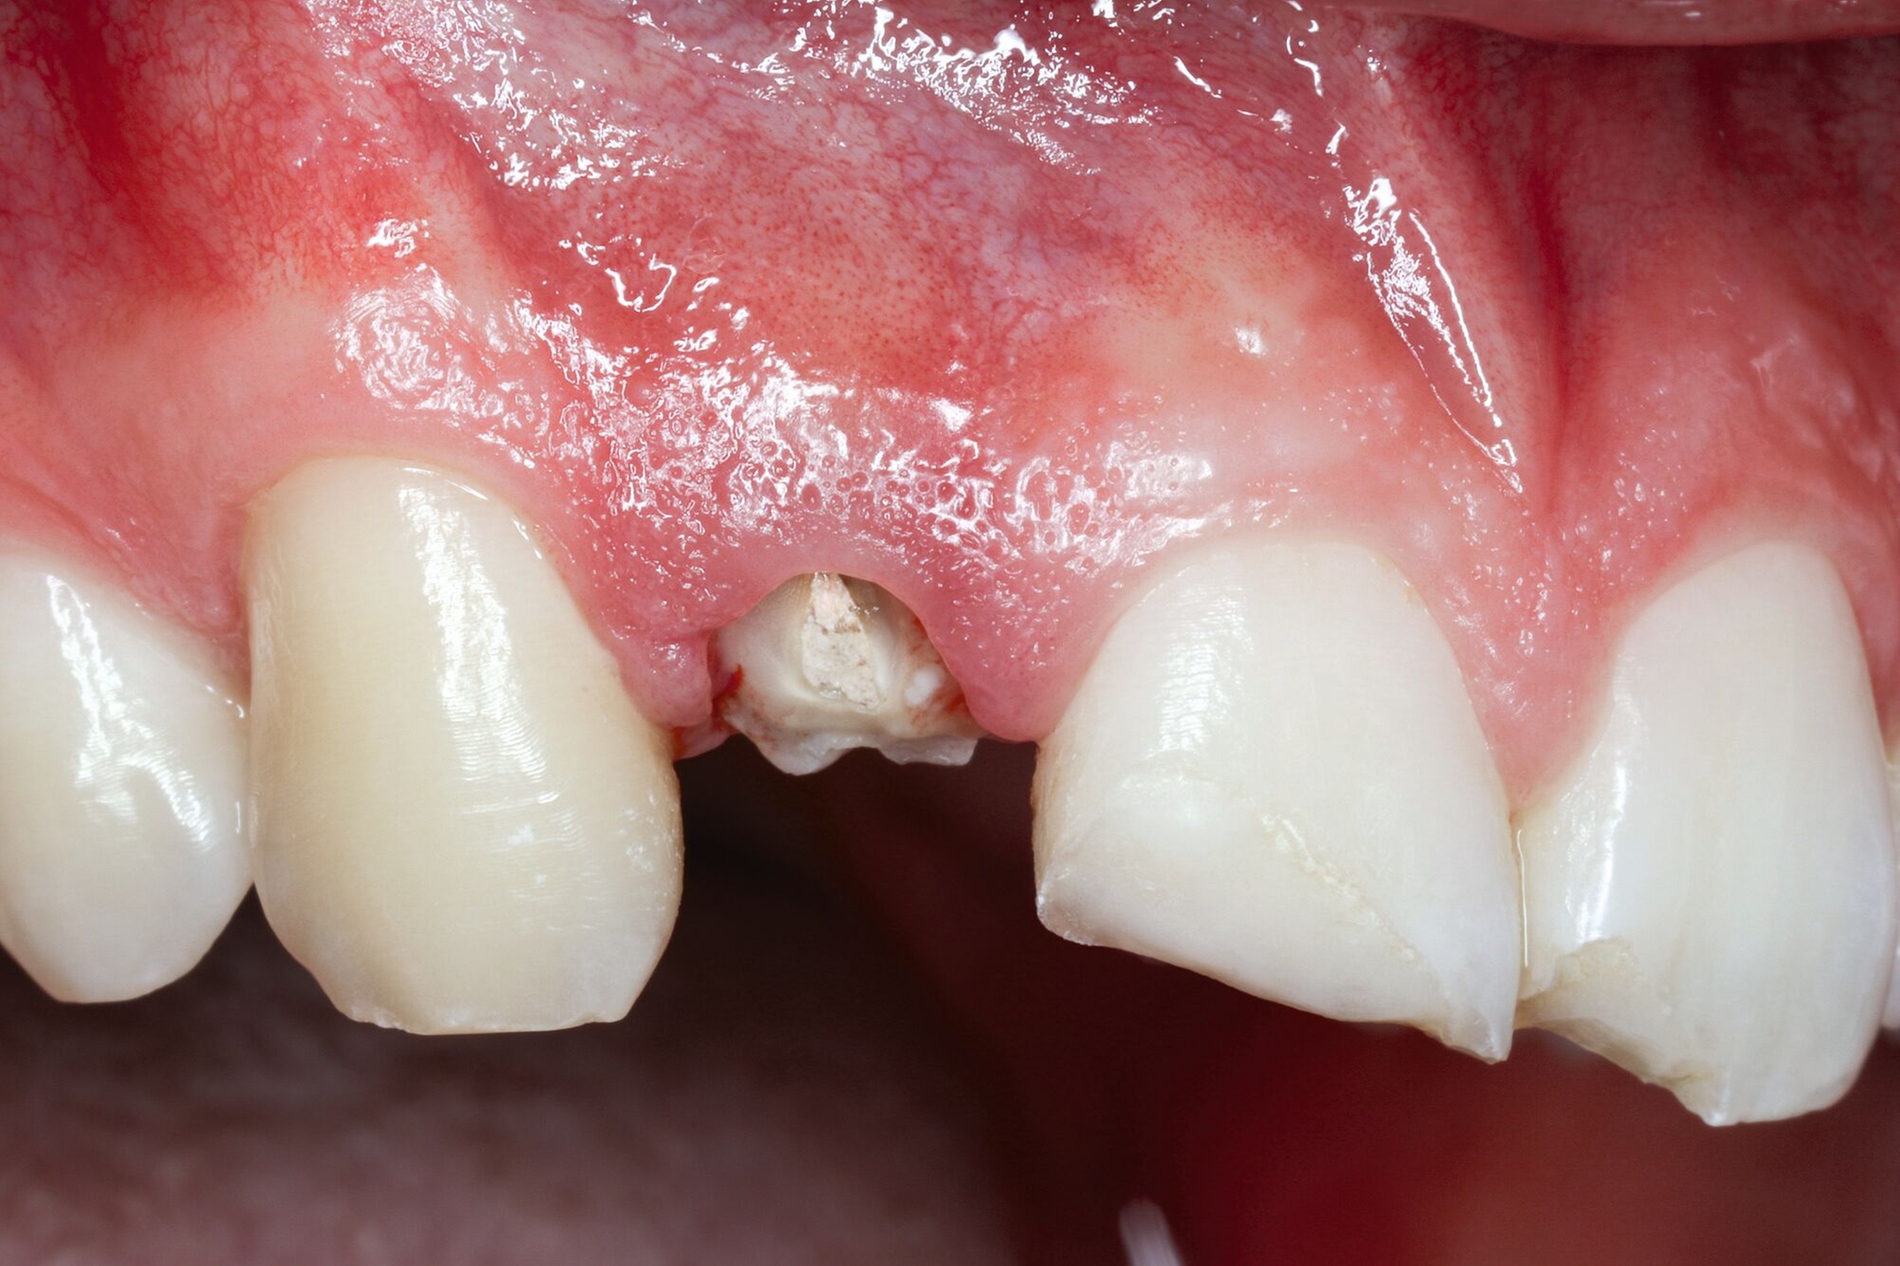

Alternativ dazu bietet sich die Koronalverlagerung der Defektgrenze mit gleichzeitiger Wiederherstellung der biologischen Breite durch eine kieferorthopädische (siehe Teil 5 der Fortbildung „Dentales Trauma“: Kieferorthopädische Aspekte) oder die chirurgische Extrusion an (Abbildung 2).